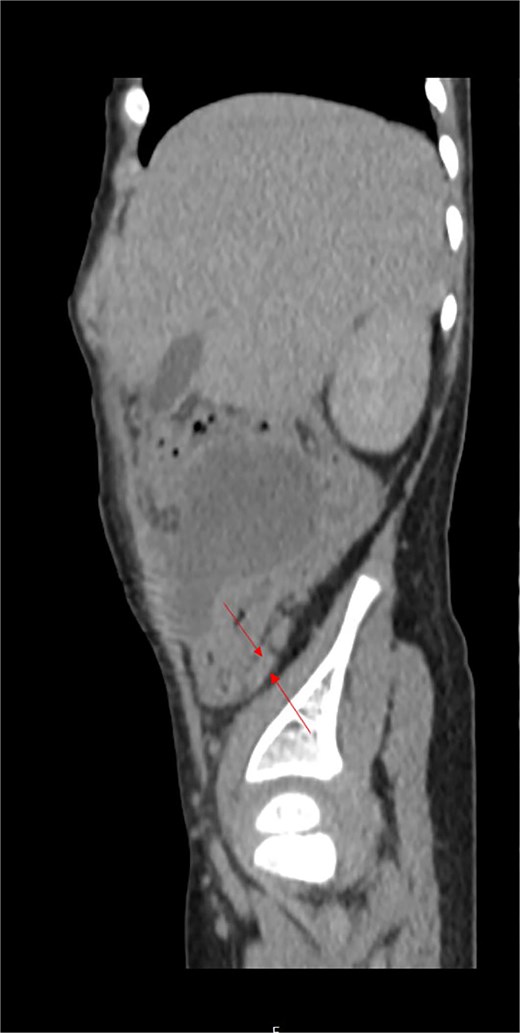

On examination, he was febrile, tachypneic, tachycardic, and hypotensive. Abdominal examination revealed a rigid abdomen with a palpable mass and marked tenderness and guarding in the right abdomen. Laboratory results indicated a leukocyte count of 19 × 109/μl, significantly elevated C-reactive protein (210 mg/dl), and a platelet count over 1 000 000/mm3, with normal coagulation tests. Abdominal ultrasound revealed echogenic fluid, prominent and hyperechoic mesenteric and omental fat, and a mass occupying the right abdomen from the subhepatic region to the pelvis. Contrast-enhanced CT of the abdomen confirmed a right abdominal mass adherent to the posteroinferior surface of the liver’s right lobe, cecum, terminal ileum, and right pelvis (Fig. 1A and B), but the appendix was not visualized. Inflammatory changes in the adjacent mesenteric fat were also noted.

(A) Contrast-enhanced abdominal CT in coronal and axial scans showed an irregularly shaped mass in the right abdomen (labeled) in the form of extensive inflammatory mass which is in the close contact with the inferior liver surface, involving parts of ascending colon, cecum, and terminal ileum. (B) Retrocecal tubular structure (labeled) inseparable of dorsal wall of coecum which can correlate to the operative findings of second appendix.

Following fluid resuscitation and antibiotic administration, a laparotomy was performed via a McBurney’s incision. Intraoperatively, purulent peritonitis with fibrin-purulent membranes and a diffuse mass in the right abdomen were observed. The appendicular infiltrate and periappendicular abscess extended from the subhepatic region to the right pelvis (Fig. 1A and B). The surgical treatment of periappendicular abscess included the evacuation of all visible pus and exudates and conducted a thorough rinse with warm saline until the outflow was free of contaminants and the operation bed was clean. Despite technical challenges due to adhesive bowel loops, distorted anatomy, and inflammation affecting a wide area in the abdominal cavity—including the cranial position of the appendix on the cecal tenia above the ileocecal valve—we successfully performed an appendectomy, submitting the fragmented perforated appendix for histopathological analysis. During further exploration, a second, retrocecal appendix approximately 30 mm long was found, attached to the cecum without visible signs of inflammation, and was resected.

Postoperatively analyzed preoperative contrast-enhanced sagittal abdominal CT scan detected a retrocecal 24.1 mm long tubular structure (a smaller second secondary inflamed appendix) with a transverse diameter of 5.6 mm and a wall thickness of 1.8 mm adherent to/inseparable from the dorsal wall of the cecum (labeled).